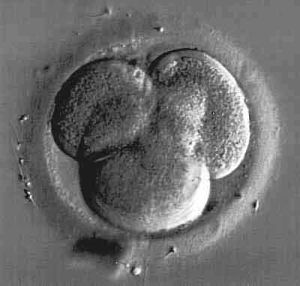

Hundefötus 39 Tage alt

Quelle: National Geographic

ab dem 35. Tag - ca. 42. Tag: Bei der Hündin kann man eine Vergrößerung des Bauchumfanges feststellen, wenn ein Wurf durchschnittlicher Größe vorhanden ist. Die Zitzen beginnen sich zu vergrößern und heben sich ab